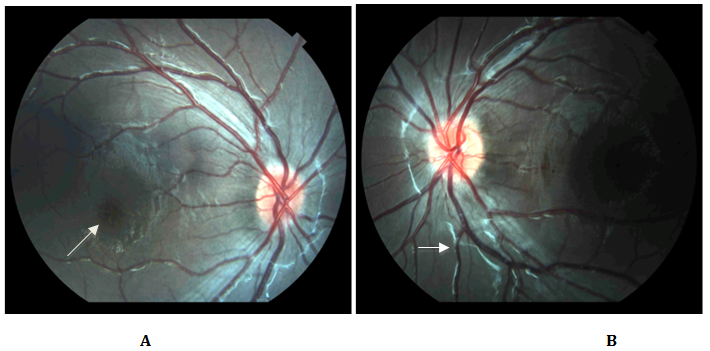

The visual acuity in patients with XLRS varies greatly. It is known that in the initial stages of the disease, the central vision is usually normal but when the schisis starts occurring, usually in the first two decades of life, it may decrease to 20/200.1,2 Most young adults present a visual acuity of 20/70. A regular trait found in these patients that has previously been called the hallmark of the disease is the presence of maculopathy. It consists of the finding of foveal schisis which consists of small, cystoid spaces and fine radial striae found in the central macula. Additional findings include peripheral retinoschisis, pigmentary deposits, vitreous hemorrhages, tractional complications, vascular sheathing and a b-wave reduction on the electroretinogram.1−5 In over50% of patients that present with peripheral retinoschisis, it is found in the inferotemporal quadrant.6,7 Figure 1A, 1B & Figure 2A & 2B present the fundus photographes of two brothers with the X linked retinoschisis. Ocular examination revealed stellate maculopathy with foveal retinoschisis bilaterally and sheathing of blood vessels.

Figure 1 (1A) Six year old male. Right Eye and (1B) Left Eye. Foveal radial streaks and sheathing of blood vessels. (1A) Arrow signals macular schisis that gives the impression of a star like pattern. (1B) Arrow signaling vascular attenuation or sheathing.

Figure 2 (2A) Right Eye. Four year old male (2B) Left Eye. Examination revealed bilateral foveal retinoschisis and blood vessel sheathing. (2A) Arrow signaling to the macular stellate spoke like appearance.